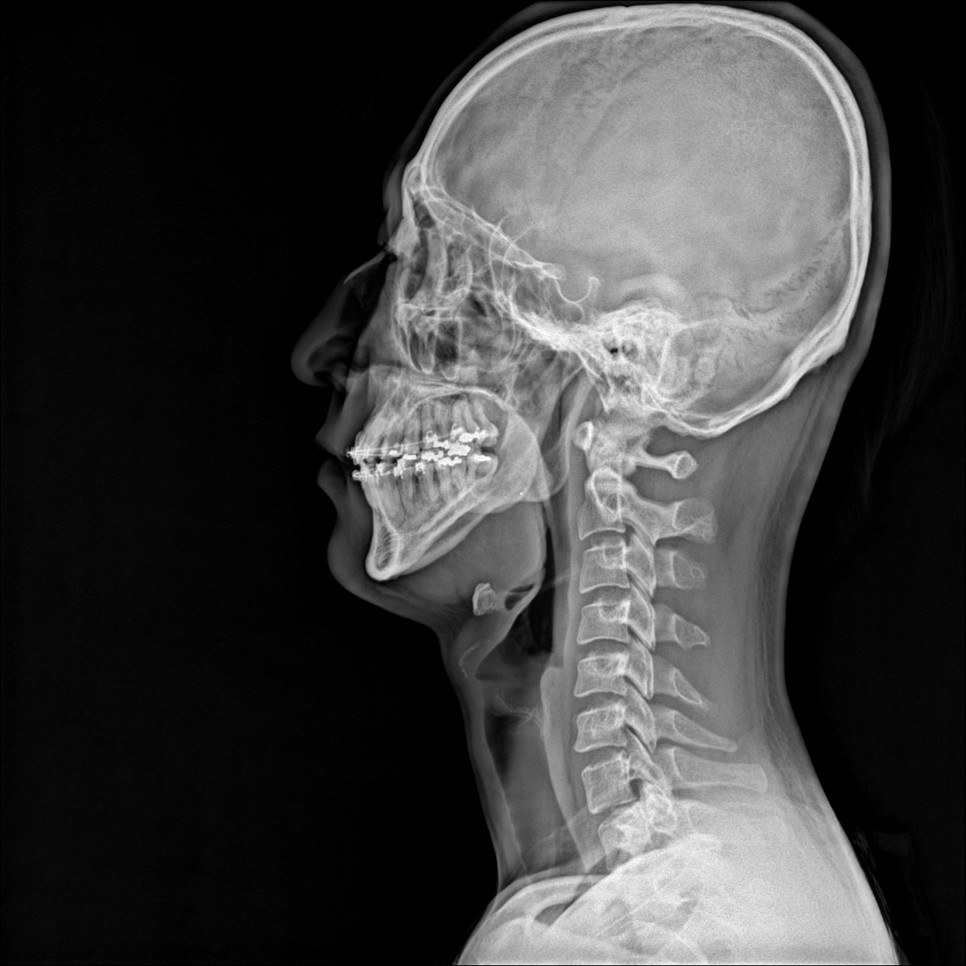

환자의 경추를 보면 정상적인 c 커브가 아니라 곧게 열린 일자 상태를 나타내고 있었습니다.

그리고 심각한 수준은 아니지만, 목의 균형이 한쪽으로 치우쳐 있는 것을 확인할 수 있었습니다.